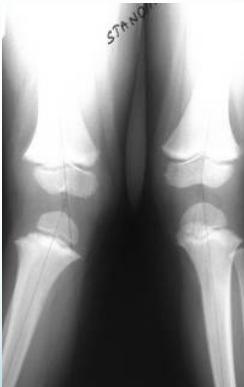

Radiological Assessment

Indications: X-ray when severe or possibly pathologic

Recommended Views:

- Standing AP film: Long film (hips to ankles) with patellae directed forwards

Radiological Parameters to Assess:

- Medial Physeal Slope

- Femoral-Tibial Axis